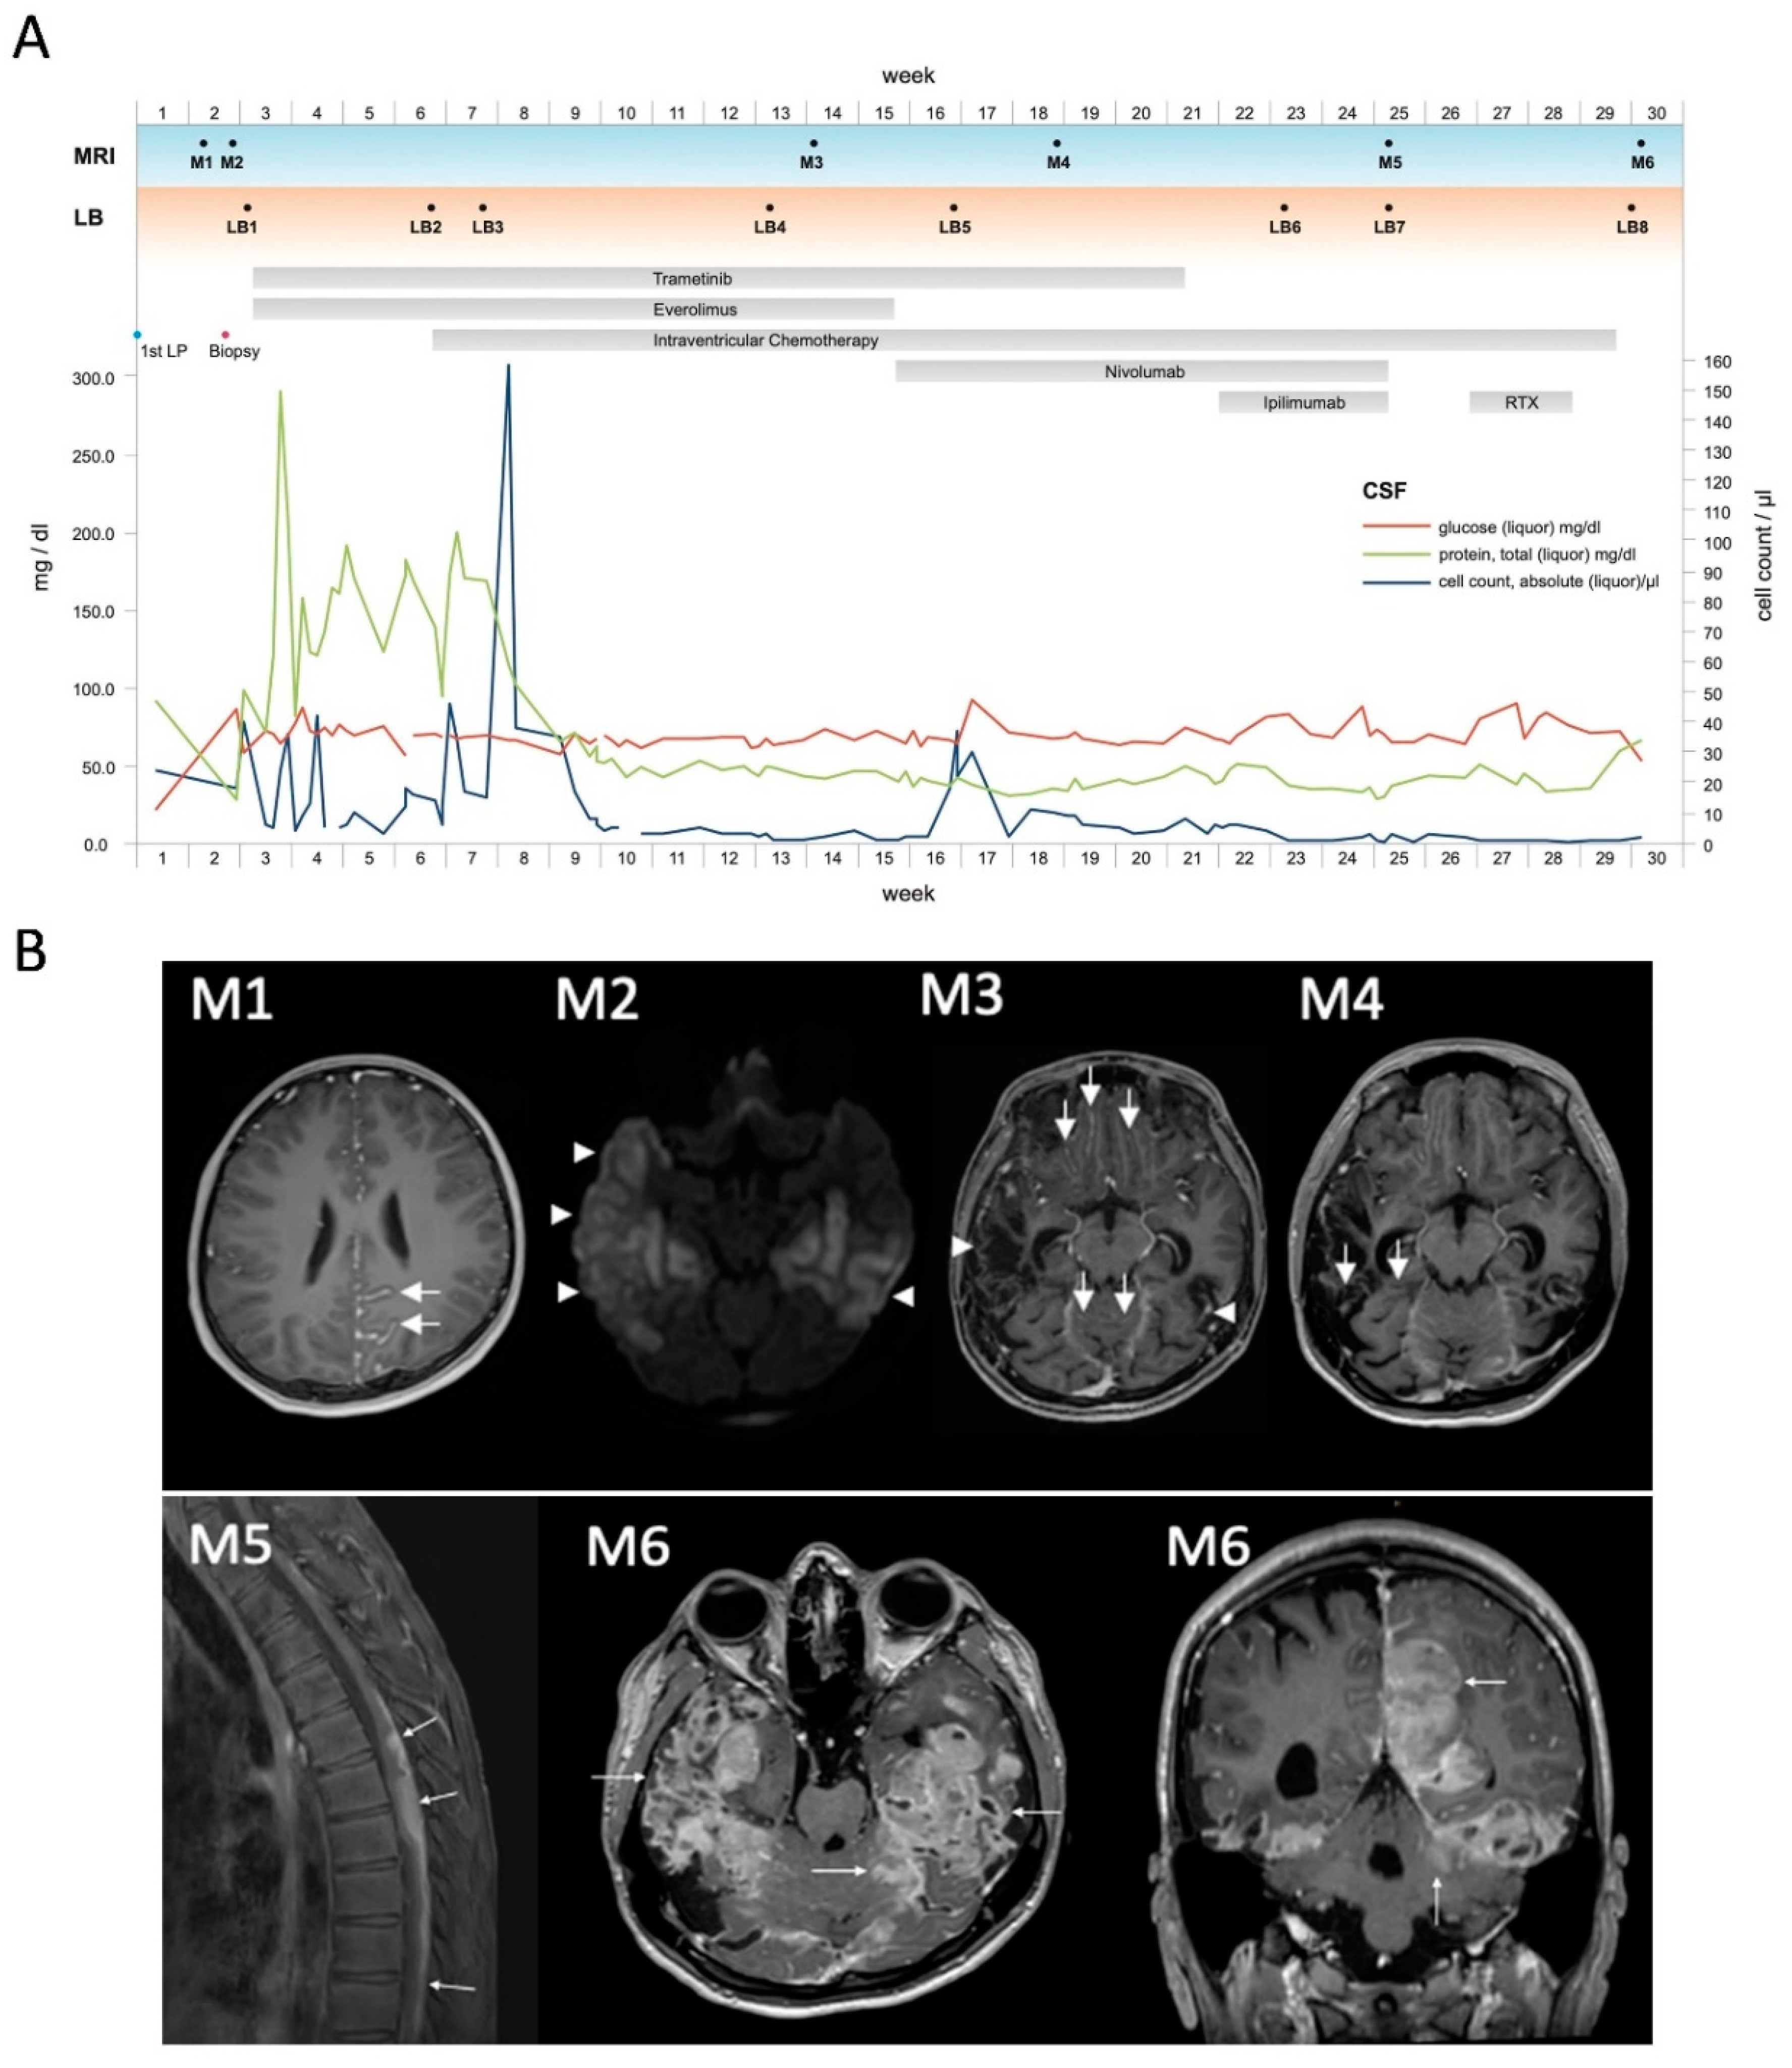

3.1. Illustrative Case

3.2. Clinical Characteristics of PDLMM

3.3. Detection of NRAS-Mutant cfDNA via Liquid Biopsy